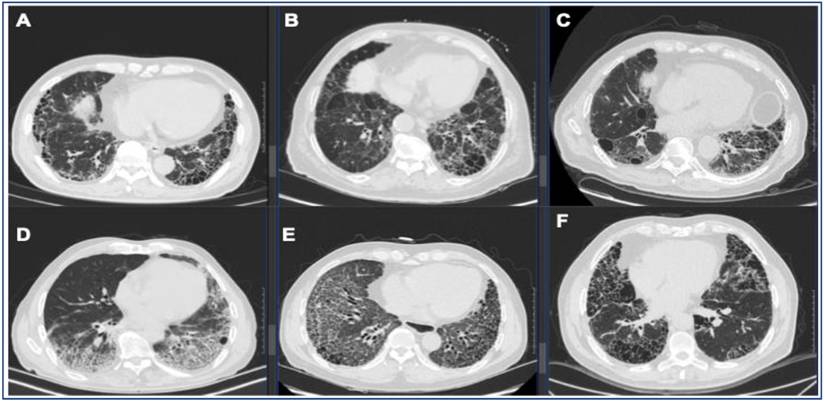

Figure 2

Representative UIP pattern on HRCT in IPF and secondary UIP. (A) IPF, (B) fHP, (C) RA-ILD, (D) pSS-ILD, (E) SSc-ILD, (F) AAV-ILD. Radiologic UIP pattern is defined as basilar, subpleural distribution of reticulation and traction bronchiectasis with honeycombing and without features incompatible with UIP.